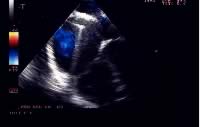

Ai pazienti viene somministrato antibiotico a largo spettro prima e per 24/48 ore dopo la procedura. Per sei mesi, in attesa della completa endotelizzazione del dispositivo, il paziente effettuerà terapia antiaggregante con aspirina alla dose di 5 mg/Kg/die e profilassi dell’endocardite batterica. Nei pazienti adulti sono sufficienti 100 mg di ASA/die (Tabella 2). Il follow-up prevede una radiografia del torace in AP ed LL ed un esame ecocardiografico transtoracico il giorno successivo alla procedura (Figura 5). In questa stessa giornata, in assenza di complicanze, il paziente può essere dimesso.